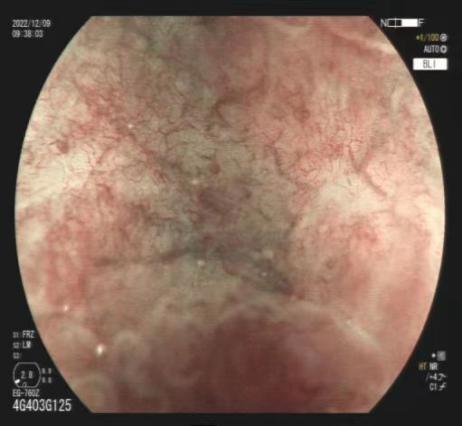

二、激光放大染色内镜

可清晰显示胃肠黏膜的腺管开口和微细血管等微细结构的变化,能比较准确地反映病变组织的病理学背景,区分增生性、腺瘤性和癌性病变,提高平坦和凹陷性早期癌的检出率,对消化道疾病的诊断及治疗具有重要的价值。

放大内镜下可见不规则微结构 BLI模式下可见不规则微血管